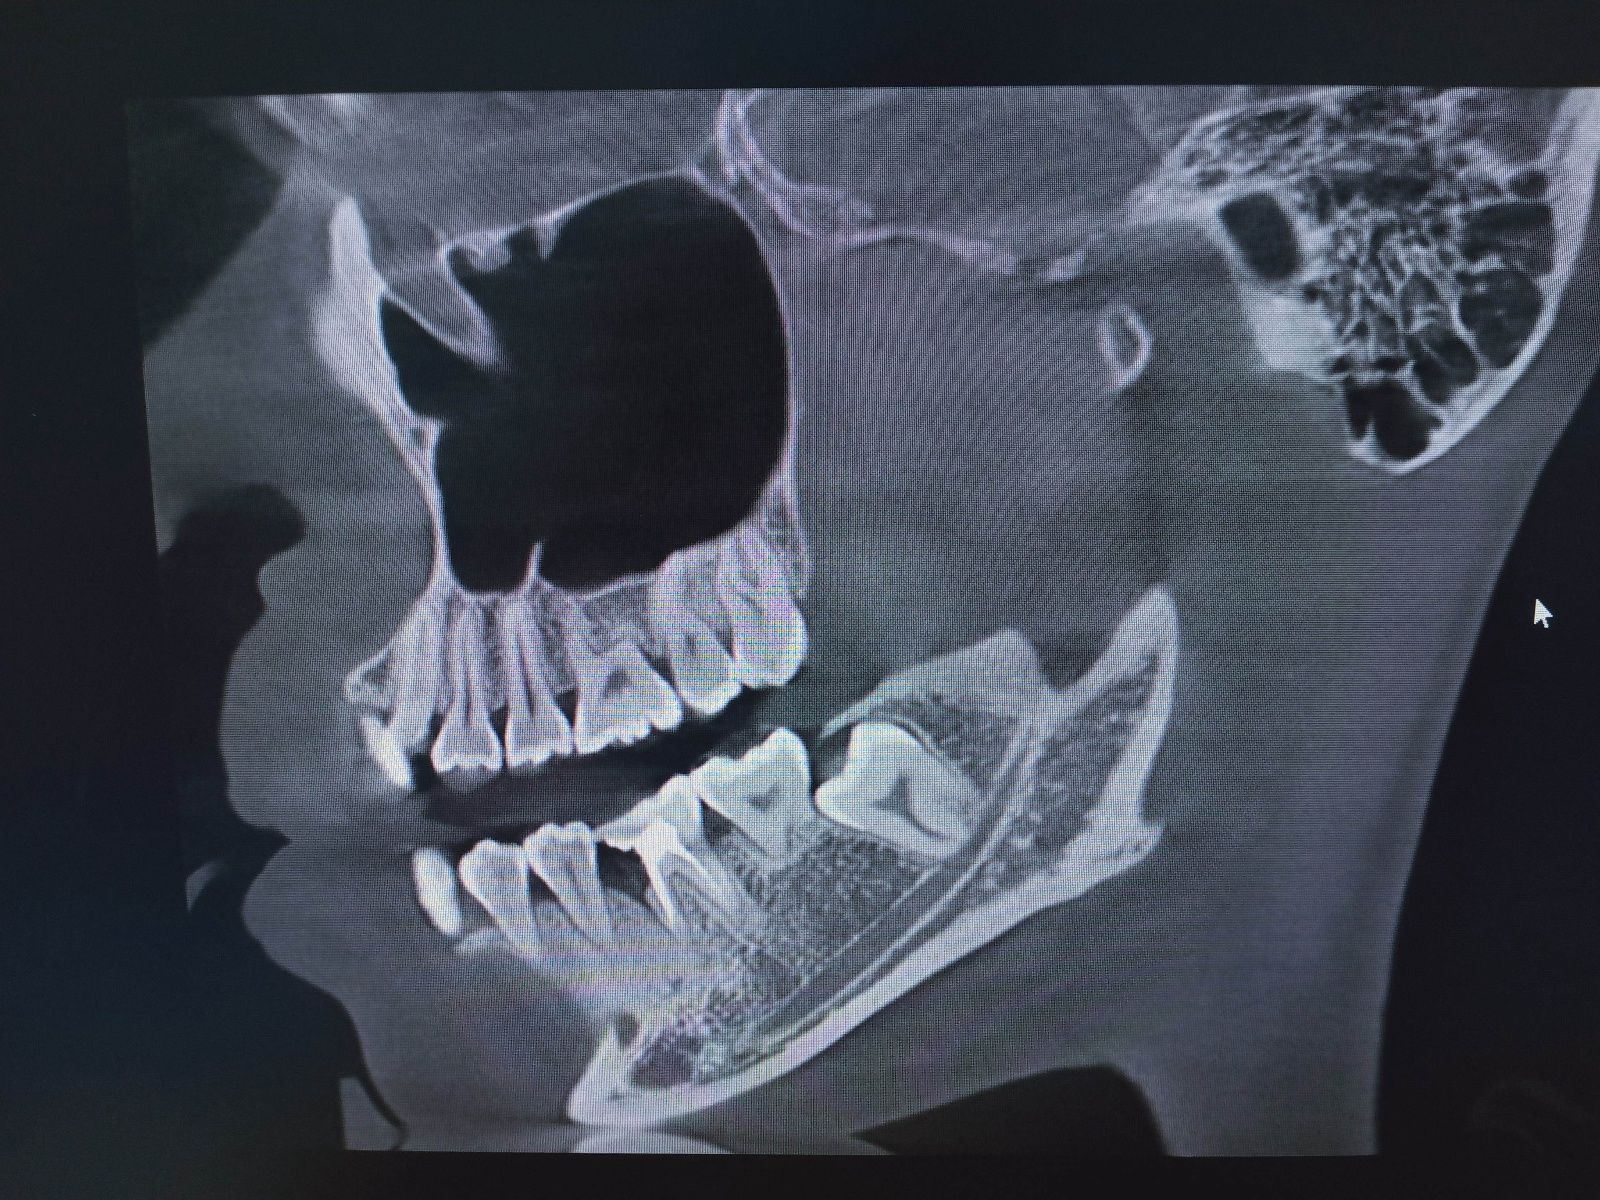

2、口腔CT(锥形束CT):可从三维角度对组织情况进行反映,准确清晰地诊查各组织的健康状态,病损范围及与周围组织间的关系以及发现更加细微的病变,诊查各类阻生牙的位置状态及与临近的神经和窦腔的位置距离,协助医师们在进行术前方案设计以及术后科学评价,还可清晰地检查牙槽骨内的病损。

目前口腔健康日渐得到广大群众的关注;口腔疾病的鉴别诊断除了有症状区别之外,在放射影像上还有很大的区别。因此为了我院口腔科在工作中更好的鉴别诊断口腔疾病以及增加患者在解决疾患上的体验感,引进口腔CBCT。口腔CBCT可以用于鉴别诊断各类型的口腔颌骨囊肿、阻生牙、多生牙、颞下颌关节的病理性损坏及错颌畸形等。

接下来简单介绍一下口腔CBCT所拍摄的各类影像检查

1、全景片(曲面断层片):适用于观察全口牙的健康状况、上下颌骨肿瘤、外伤、畸形、全口牙槽骨吸收程度,以利于检查出肉眼无法观察到的病损。

3、头颅侧位片:用于展示颅骨和牙的侧方形态,可清晰具体诊断出各类牙的错颌畸形,口腔正畸医师通过该片测量出重要的参考数据进行一对一的牙矫正方案的设计以便达成更有效的正畸治疗效果。

4、颞下颌关节的检查:可清晰地检查双侧颞下颌关节的关节组织健康状态,关节内骨质的病损。